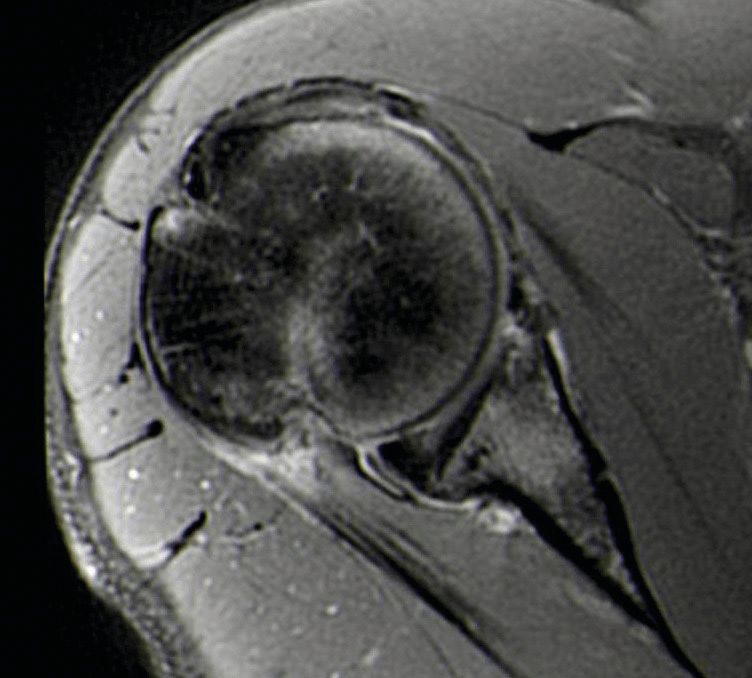

For the purpose of better assessing the risk of HSL relative to the glenoid, the glenoid track concept was introduced [12]. The glenoid track is the area of posterior humeral articular surface in contact with the glenoid when the arm moves along the posterior end-range of movement. If the HSL stays within the glenoid track (on-track), no engagement/ dislocation should occur. However, if it goes out of the glenoid track (off-track), the anterior rim of the glenoid may fall into the HSL, causing a dislocation [13]. Figure 2.

The HSL is related to the end-range of motion. When the shoulder is in abduction and external rotation the humeral defect can engage with the anterior rim of the glenoid and lead to a dislocation. Therefore the risk of engagement and dislocation is related to the position and the size/depth of the HSL. This is the concept of engaging and non-engaging lesion [11].